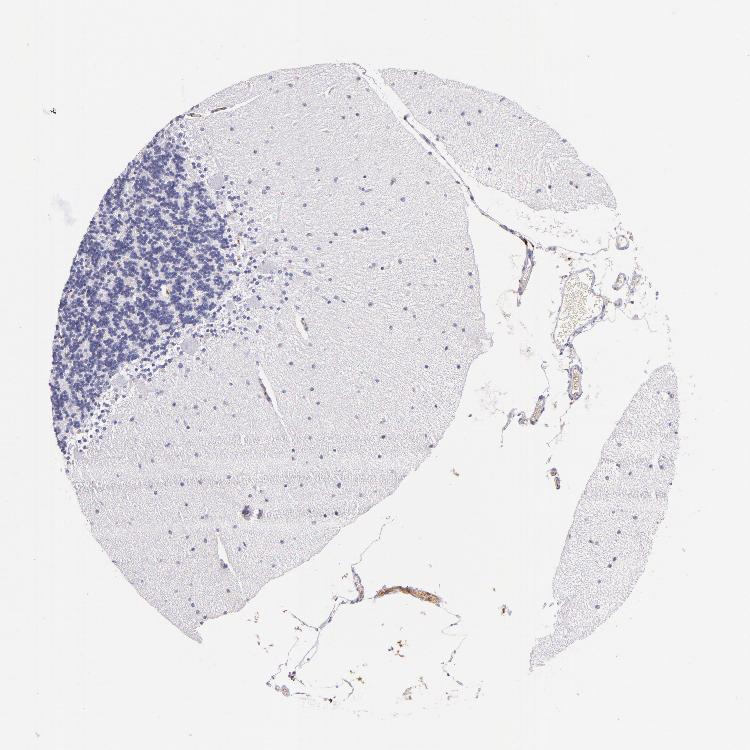

CEREBELLUM - Antibody stainingi

Antibody staining in the annotated cell types in the current human tissue is reported as not detected, low, medium, or high, based on conventional immunohistochemistry profiling in selected tissues. This score is based on the combination of the staining intensity and fraction of stained cells.

Each image is clickable and will lead to virtual microscopy that enables deeper exploration of all samples and also displays staining intensity scores, fraction scores and subcellular localization as well as patient and tissue information for each sample.

Antibody HPA001616Antibody HPA001645Antibody CAB009809

Purkinje cells Not detectedNot detectedNot detected

Cells in granular layer Not detectedNot detectedNot detected

Cells in molecular layer Not detectedNot detectedMedium